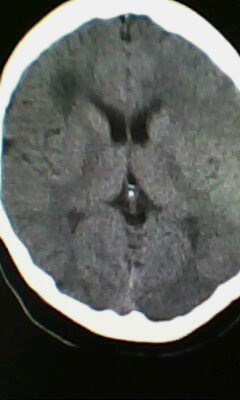

标题: CT25171:患者间断性头痛 无外伤史 [打印本页]

标题: CT25171:患者间断性头痛 无外伤史

右侧额叶脑穿通畸形囊肿。

图不清,有灰质异位吗?与脑裂畸形鉴别

囊肿引起的脑穿通。

右侧额叶脑穿通畸形囊肿。支持!

那就说囊肿不就行了吗,中间有囊肿了还可以叫穿通畸形了吗?那中间要是有个肿瘤是不是可以叫穿通畸形肿瘤呢

以前不光叫穿通畸形吗,谁没事给改了,改就改吧,反正我说了不算根着改就行了,这一病多名的问题太讨厌了